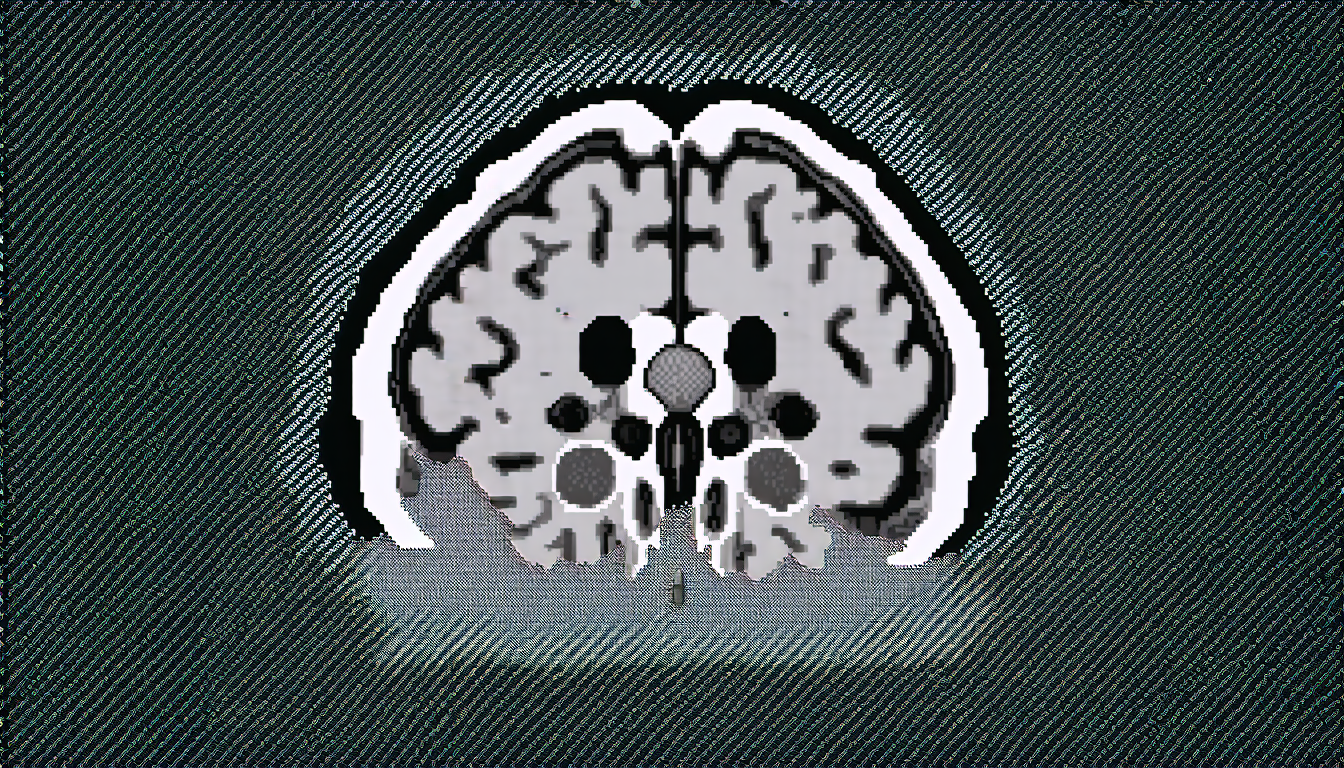

The researchers tested their approach on a range of different datasets, including MRI scans of the brain and spine. In each case, they found that the synthetic images were highly accurate and effective in capturing the key features of the real-world data.